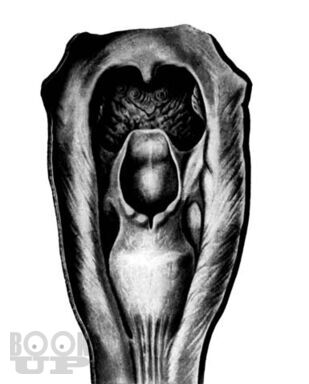

Книга П.В. Власова посвящена традиционным методам рентгенологического исследования пищеварительного тракта. В последние 20 лет периодическая печать заполнена публикациями, посвященными новым, модным и актуальным вопросам применения новейших методов лучевой диагностики, таких как ультрасонография, компьютерная и магнитнорезонансная томография. Между тем как подавляющее большинство рентгенологов в своей практической работе используют традиционные методы рентгенологического исследования, являющиеся базовыми, первичными в клинической диагностике различных заболеваний.